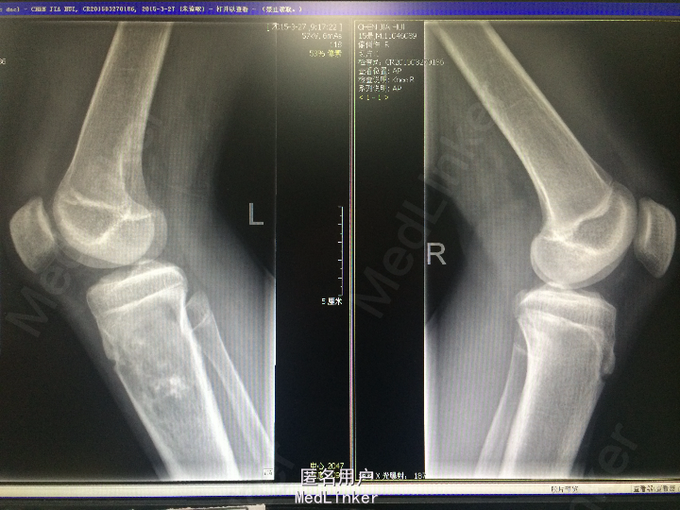

青少年男性 主诉:扭伤左小腿后反复疼痛4月,加重伴肿胀2周。 病史:患者于4月前跳舞时不慎扭伤左小腿上段,后出现左小腿疼痛,呈酸痛性质,呈间歇性,无明显加重及缓解因素,无夜间疼痛加重,无伴发热、盗汗,当时程度较轻,未予重视。2周前患者无明显诱因出现症状加重,并觉左小腿上段肿胀,无局部红肿、发热,无伴关节活动受限,遂于当地医院就诊,查X线提示左胫骨近侧干骺端占位性病变,考虑来源于软骨类肿瘤可能性大。行左小腿MR平扫+增强提示:左侧胫骨上段占位性病变 ,考虑恶性骨肿瘤(骨肉瘤)。现为进一步诊治就诊于我院,患者自起病以来,无发热,无咳嗽、咳痰,大小便正常,体重无明显变化。

诊断:恶性骨肿瘤:骨肉瘤? 处理:完善相关检查,局麻下行左胫骨肿物穿刺活检术,病理诊断为骨肉瘤。遂进行AP方案诱导化疗,其中吡柔比星针(合)40mg d1-2+顺铂针 30mg d1-5,过程顺利。后患者肿瘤疼痛加重,予止痛治疗,住院期间下床时不慎扭伤左下肢后疼痛加重,行左膝关节X光检查提示病灶部位骨折,断段对位对线上课,暂予止痛、夹板固定,择期手术治疗。后行全麻下左大腿截肢术。术后予止痛、补液、预防感染等治疗,患者恢复良好。